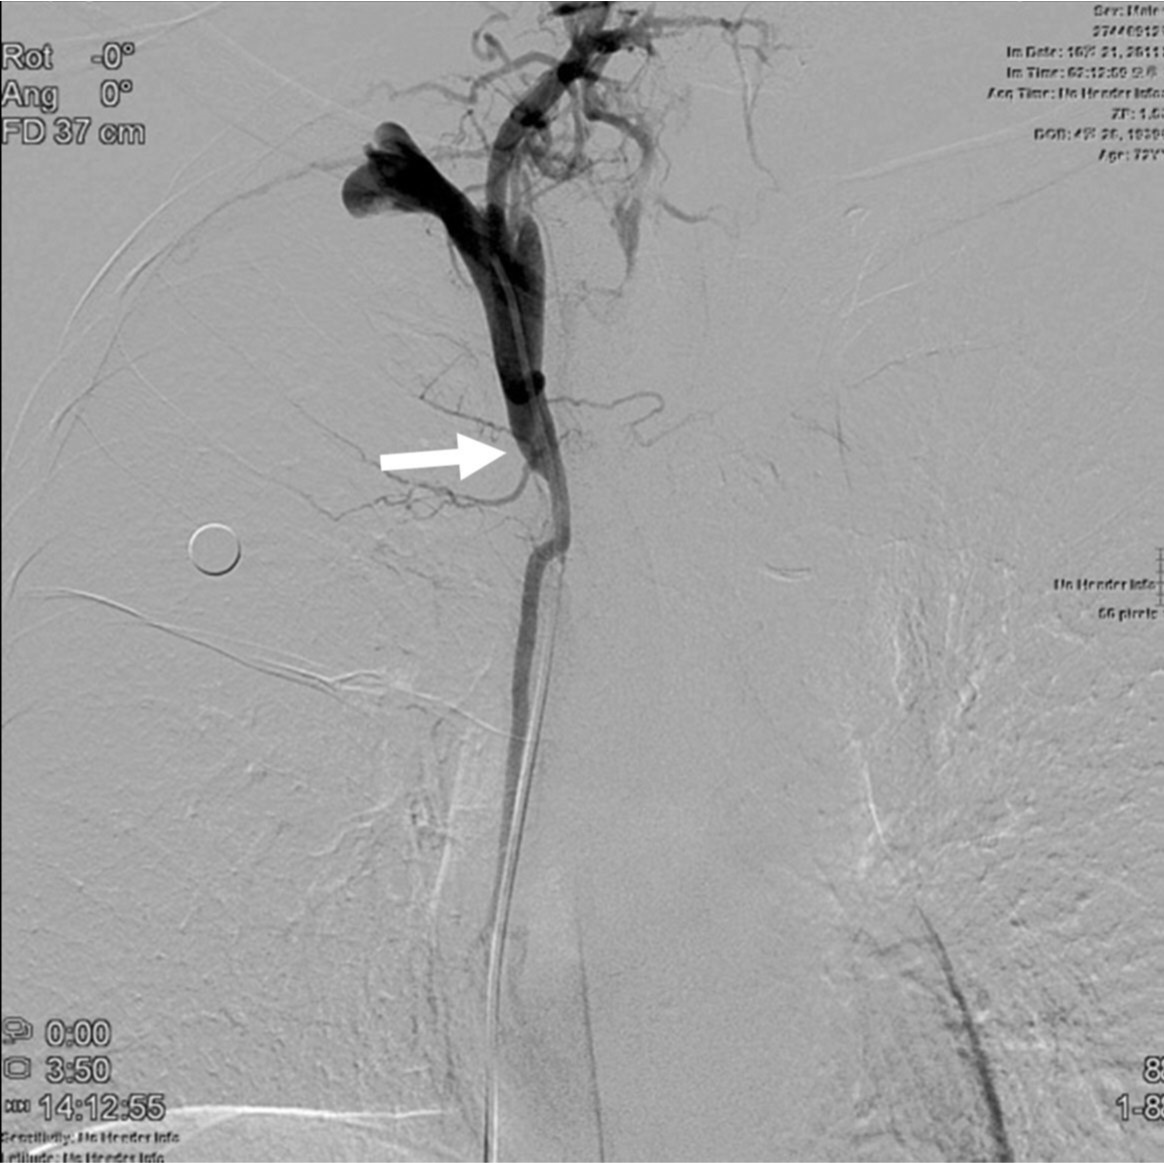

우측 대퇴정맥을 천자하여 7Fr sheath를 삽입하였고, 5Fr 카테타와 0.035-인치 유도철사를 상대정맥 근위부까지 전진한 다음 roadmap 영상하에 좁아진 상대정맥을 통과하였음. 5Fr 카테타를 우측 상완두정맥(right brachiocephalic vein)에 위치한 상태에서 시행한 정맥조영술에서 우상완두정맥 근위부에 위치한 협착 원위부 경계는 확인되었지만 심한 협착으로 인해 협착 근위부 경계는 확인이 안되었음(Fig. 2). 0.035-인치 Rosen 유도철사(Cook, Bloomington, USA)를 따라 6Fr Envoy 카테타(Cordis, Miami, USA)를 협착부위에 위치시킨 상태에서 정맥조영술을 시행하여 상대정맥에 위치한 협착 근위부 경계를 확인하였음(Fig. 3). 협착부위에 14mm x 60mm selfexpandable stent(SMART, Cordis, Miami, USA)를 설치하였고, 협착이 심하여 8mm x 40mm 풍선카테타(Synergy, Boston Scientific, Natick, USA)로 협착부위를 먼저 넓힌 다음 4mm x 40mm 풍선카테타(XXL balloon, Boston Scientific, Natick, USA)로 풍선확장술을 시행하였음(Fig. 4). 종양에 의한 협착이 심하여 풍선이 완전히 펴지지는 않았지만 풍선확장술 후 시행한 우내경정맥조영술에서 스텐트를 통해 심장으로 혈류유입이 원활하였고(Fig. 5), 우내경정맥과 스텐트 근위부 상대정맥의 혈압을 측정하였을 때 3mmHg의 혈압 차를 보여 시술을 종료하였음. 환자는 임상증상이 호전되어 시술 2일 뒤 퇴원하였고, 시술 후 6개월이 경과할 때까지 스텐트의 patency는 잘 유지되고 있었음(Fig. 6).

Fig. 2.

Fig. 2. On right brachiocephalic venogram, the distal end(arrow) of the stenosis is only seen with no visualization of its proximal end.